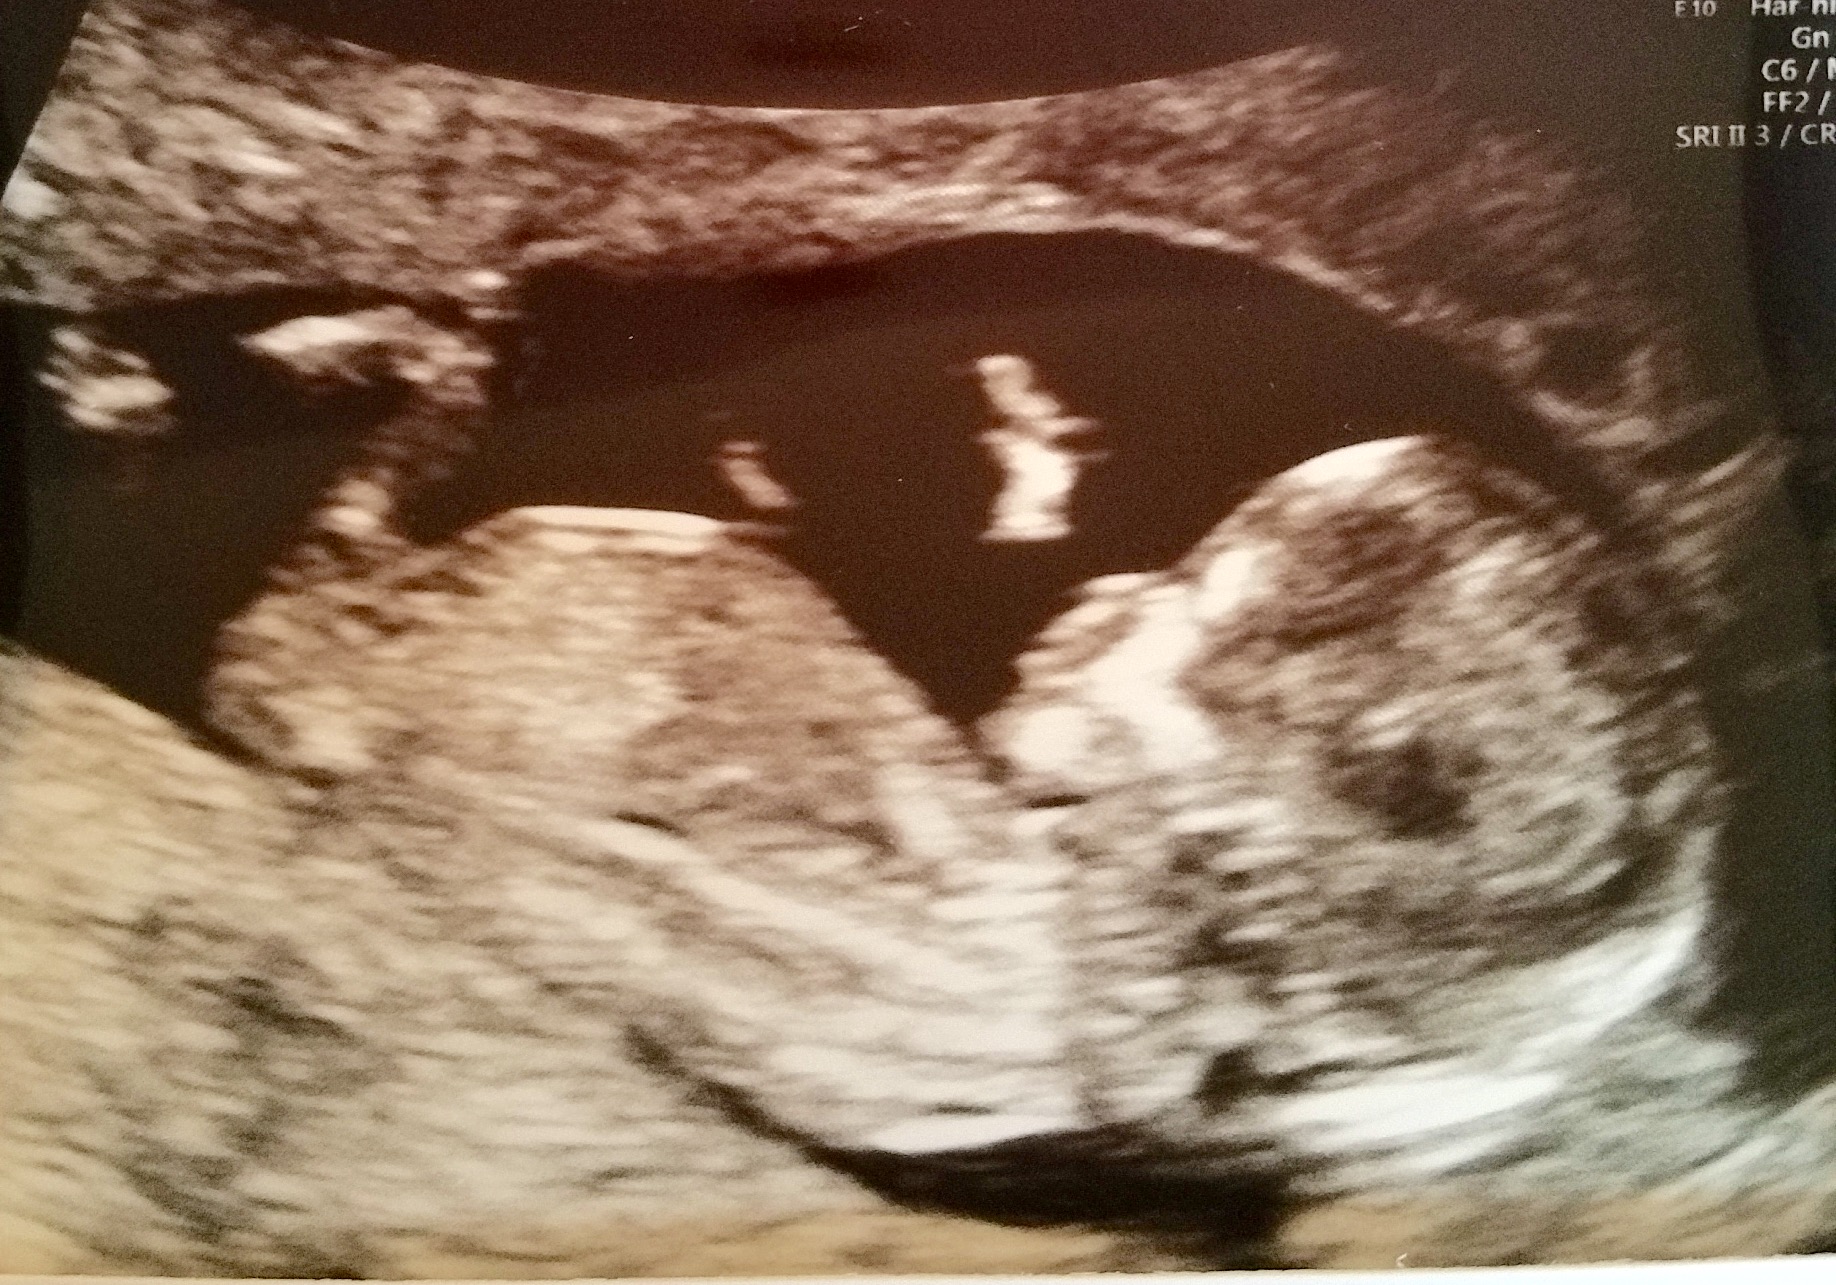

I think the nub looks boyish, but can't tell if it is actually a 'nub' or a leg!

Maybe boy

I'd guess blue x

Don't see a nub sorry. I think that's a leg.

Agree with Ksmom. I think that's a leg.

Can't makeout the nub either

I think that's probably a leg but tentatively guess boy.

I don't think you can tell, I look at it and sometimes I see girl and sometimes I see boy

Leaning boy.

cant see any nub there?!